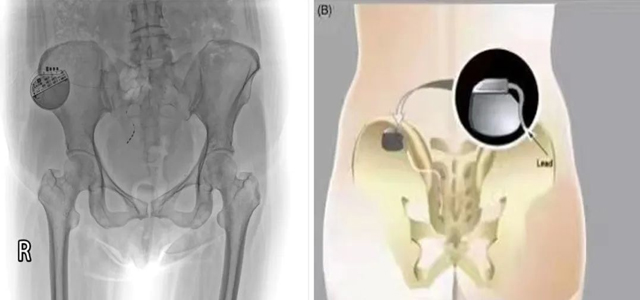

为缓解会阴及盆底疼痛给患者带来的不适感,翟春宝主任及其团队经科室讨论后决定为该患者进行骶神经调控术,并与患者及家属耐心沟通。根据综合评估,择期局麻下行一期骶神经调控器置入术。依据患者肛周感受调节控制器相关数值。

术后3月,患者自觉肛周坠胀明显减轻(自述好转70%以上),大小便控制能力较术前明显改善。患者及家属对一期调控效果非常满意,完善相关检查后行骶神经调节器植入(二期)。

骶神经调控:是指利用介入手段将一种短脉冲的刺激电流连续施加于特定的骶神经,以此剥夺神经细胞本身的电生理特性、以便人为地激活兴奋或抑制神经通路、干扰异常的骶神经反射弧,进而影响由调节盆底等骶神经支配的效应器官的行为,起到“神经调控”的作用。

骶神经调控 (SacralNeuromodulation, SNM)作为医学科学、疾病治疗的新兴科学,是当代医学研究和临床实践的热点,是当今解决功能障碍性疾病的必需手段。